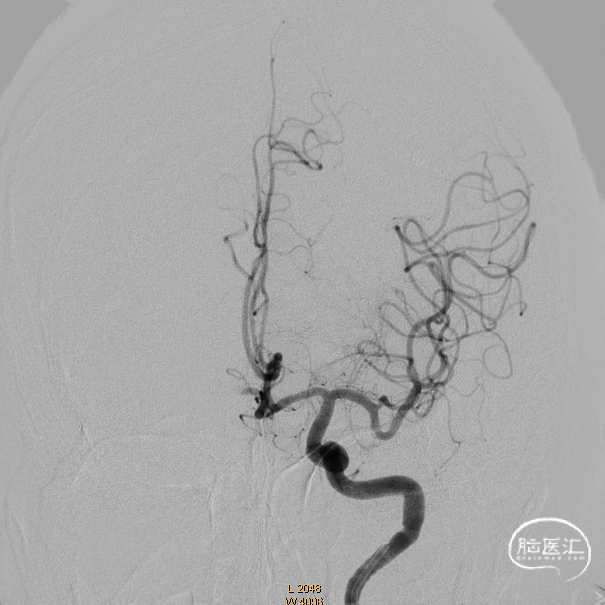

左侧正侧位造影。

后循环造影。

微导管越过闭塞部位造影证实在真腔。

术后造影,一把三级再通。